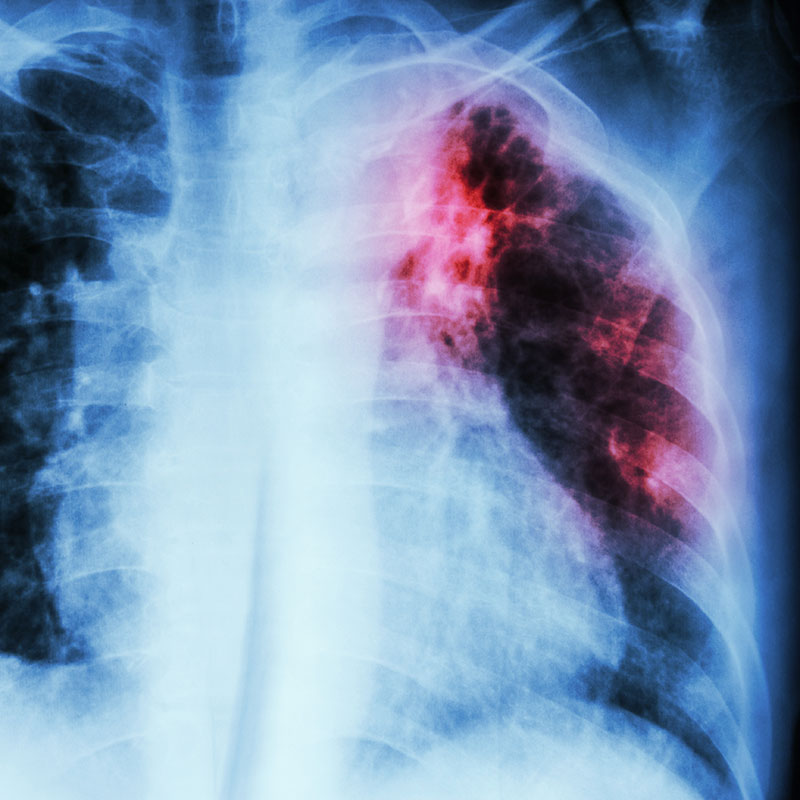

Tuberculosis is a Threat in the NCN Community

Not enough NCN Citizens understand how it is spread or the dangers of its effects. Tuberculosis is a contagious disease that generally affects the lungs, but can also affect the brain, kidneys and spine.

It is a potentially life-threatening disease that is spread through close, continuing contact with someone who has active TB. Germs from coughing and sneezing can stay in the air for hours, which means TB can take hold in conditions where there is inadequate housing, malnutrition and poverty.